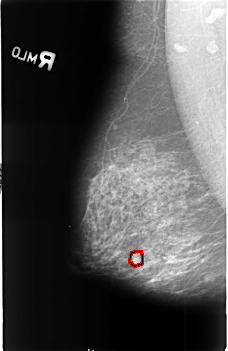

B_3406_1.RIGHT_MLO

FILE: B_3406_1.RIGHT_MLO.OVERLAY

TOTAL_ABNORMALITIES 1

ABNORMALITY 1

LESION_TYPE CALCIFICATION TYPE PLEOMORPHIC DISTRIBUTION CLUSTERED

ASSESSMENT 4

SUBTLETY 3

PATHOLOGY MALIGNANT

TOTAL_OUTLINES 1

BOUNDARY